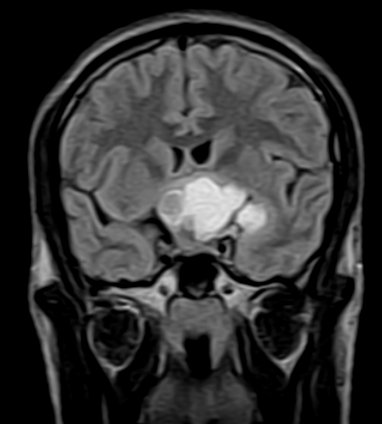

December 2005 - Craniopharyngioma

There is evidence of a lobulated extra-axial mass lesion in the suprasellar cistern. The lesion is predominantly hyperintense on the T1W images and heterogeneously hyperintense on the T2W and FLAIR images. The optic chiasm, proximal optic nerves and the pituitary stalk cannot be identified separately from this lesion. However, the pituitary gland is well identified.

Craniopharyngiomas are epithelially derived neoplasms that usually occur in the suprasellar cistern. Occasionally they occur in the sella or in the third ventricle.  They constitute approximately 3% of all intracranial tumors and show no sex predilection. Craniopharyngiomas are hormonally inactive lesions. 50% of these lesions occur in childhood or adolescence, with a peak incidence between 5 and 10 years of age. A second smaller peak is seen in the sixth decade. Patients may present with headaches and/or visual disturbances. The lesions usually exhibit a heterogeneous appearance with presence of a cystic and/or solid component. It may be hyperintense on both T1W and T2W images. The lesions may encase nearby cerebral vasculature. The solid portion may be calcified. On contrast the solid portion usually enhances.